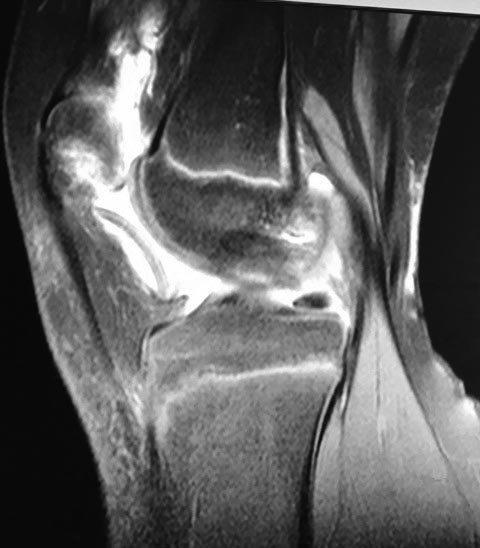

Девочка10 лет. Травма 1 месяц назад – упала на горке. Лечилась консервативно. По данным МРТ имеется остеохондральный дефект наружного мыщелка бедренной кости и свободный костно-хрящевой фрагмент размером 3 см. в диаметре. Девочка 10 лет. Травма 1 месяц назад. По данным МРТ имеется остеохондральный дефект наружного мыщелка бедренной кости и свободный костно-хрящевой фрагмент 3 см в диаметре.

Girl 10 years old. She fells on the hill 1 month ago. Conservative treatment. According to the MRI she has osteochondral defect of external femoral condyle and free osteochondral fragment size of 3 cm. in diameter. Optimal fixation if possible?